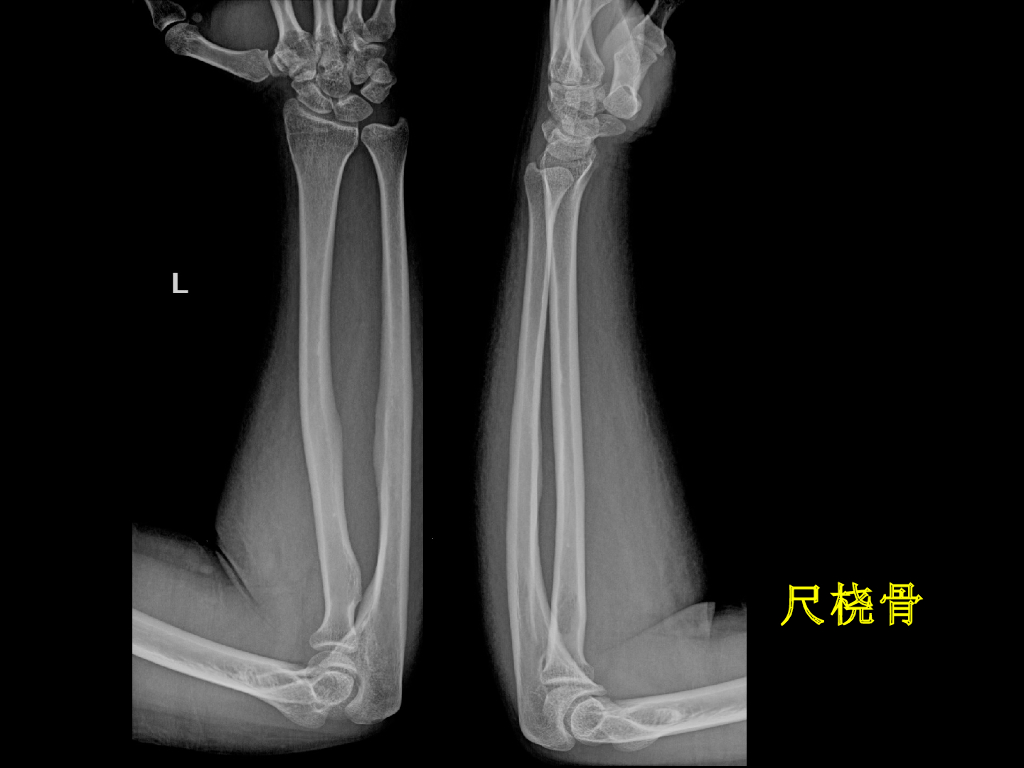

《放射诊断学》演示文稿-骨关节影像学检查与先天性畸形实习课.pdf